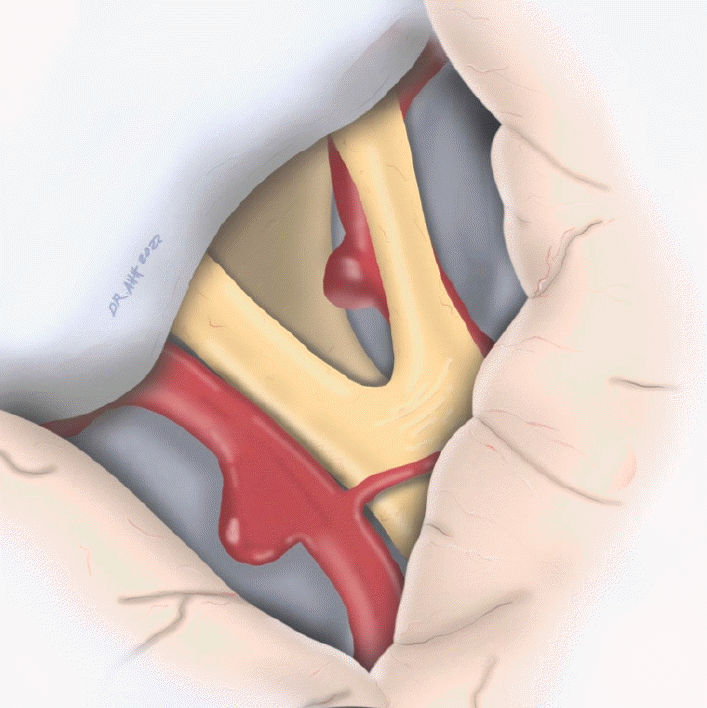

During subarachnoid dissection, a post-fixed optic chiasm with a wide interoptic space was identified (Fig. 2), which allowed a complete dissection of the arachnoid planes, with complete visualization of the contralateral aneurysm’s neck and collateral arteries of the contralateral ICA (pComm and anterior choroidal artery) (Fig. 3). After thorough, the ipsilateral aneurysm was clipped with no difficulty, assessing patency of the ICA branches (Fig. 4) with DSA (Fig. 5). Both aneurysms were permanently clipped with a 7 mm straight clip. The patient’s postoperative course was uneventful, with a sequel left oculomotor palsy.

Fig. 3.

Contralateral pComm aneurysm clipping. (A) Operative view. 1. Left ICA. 2. Contralateral aneurysm clip. 3. Right ICA and right aneurysm neck. 4. Left ICA bifurcation. 5. Right optic nerve. 6. Left optic nerve. (B) Artist drawing illustration of the contralateral pComm aneurysm clipping. pComm, posterior communicating; ICA, internal carotid arteries

Fig. 4.

Ipsilateral pComm aneurysm clipping. (A) Operative view. 1. Ipsilateral pComm aneurysm’s dome. 2. Ipsilateral clip. 3. Contralateral clip. 4. Left ICA. (B) Artist drawing illustration of the ipsilateral pComm aneurysm clipping and the contralateral pComm aneurysm clipped before. pComm, posterior communicating; ICA, internal carotid arteries